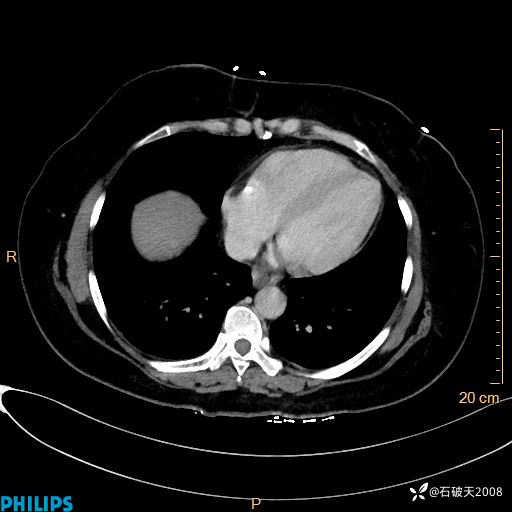

纵隔窗

动脉期